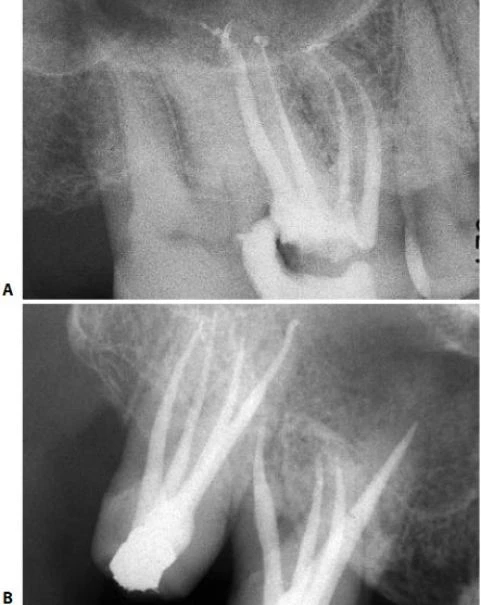

Hình 5.41. A. Phim X-quang trước điều trị của răng cửa giữa hàm trên bên phải. Lỗ chóp nằm trên cùng một mặt phẳng trên đường đi của tia X: nó có thể đối diện với mặt trong hoặc mặt ngoài. B. Phim X-quang thứ hai chụp theo hướng gần-xa cho thấy đoạn cong đối diện với mặt ngoài. Việc điều trị tủy được hoàn tất, giữ nguyên góc chụp cho phép nhìn thấy được điểm cuối cùng trên X-quang của ống tủy. C. Phim sau điều trị. Lưu ý rằng chỉ với góc chụp này mới thấy được hình ảnh tổn thương nhỏ tại chóp chân răng. D. Phim sau điều trị được chụp theo tiêu chuẩn hình chiếu. Lưu ý rằng vật liệu trám ống tủy dường như bị ngắn đi chừng 2mm và tổn thương cũng đã lành.